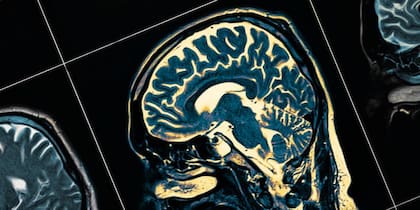

Son solo 60 las personas que hasta el momento han sido identificadas con esta condición, pero el motivo por el cual se genera aún no es del todo claro. Lo que sugieren las investigaciones realizadas es que hay un aumento en el tamaño del lóbulo temporal -el que ayuda a procesar la memoria-, como también en el núcleo caudado -el que ayuda a aprender-.